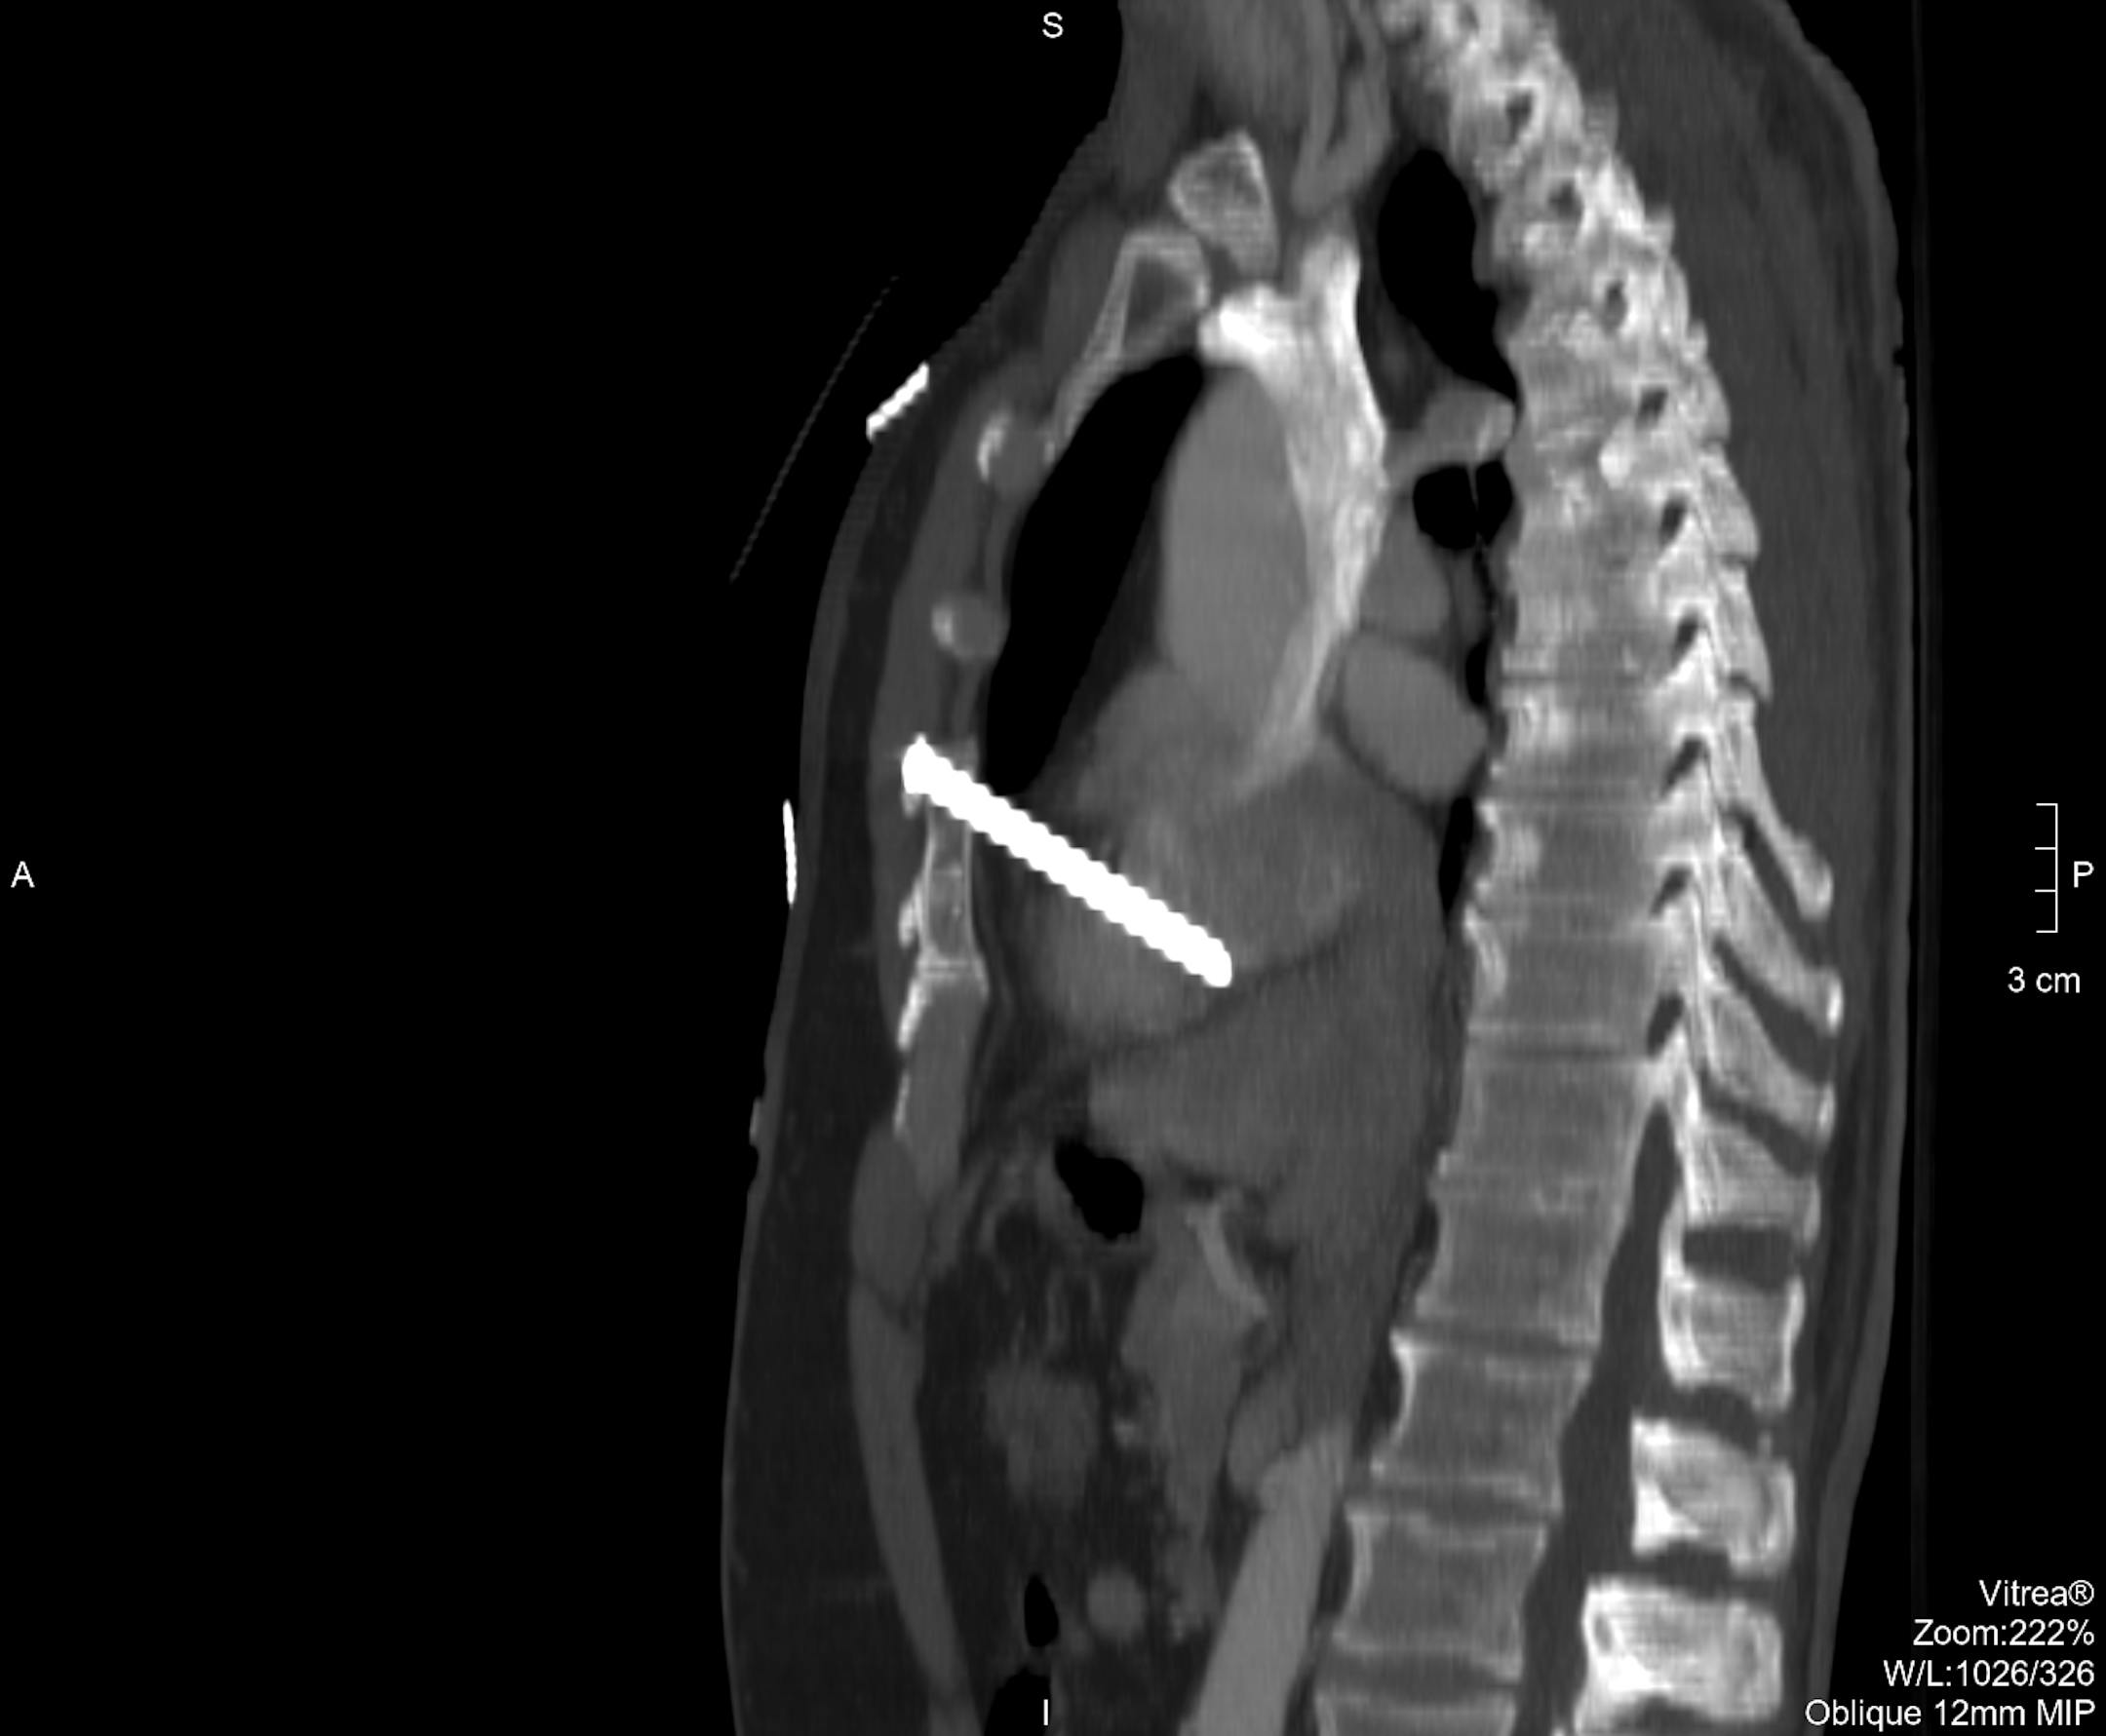

X-ray of nail in heart from Abbott Northwestern Hospital.

X-ray of nail in heart from Abbott Northwestern Hospital. (Stan Schmidt/The Minnesota Star Tribune)

Rakow was building a deck for a neighbor Friday when the 3 1/2-inch nail pierced his chest and came with 2 millimeters of a coronary artery, said Allina's Gloria O'Connell, a spokeswoman for Abbott Northwestern Hospital in Minneapolis, where he was treated.

The doctor who performed the surgery, Louis B. Louis, said, "This nail went through the front and the back of his heart, barely missing critical structures. I'm very pleased his post-operative courts has been so uncomplicated."

The doctor said Rakow "was extremely lucky, first that he was able to get to a hospital and second that the nail missed the coronary artery by about 2 millimeters twice — going in and going out," O'Connell said.

"The sternum also acted as a 2-by-4 and stopped the nail from going in deeper than it did," she added. "In the end, [the doctor] put two stitches in the heart."